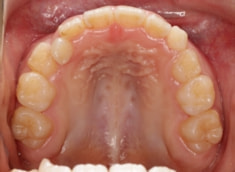

治療前

治療開始時